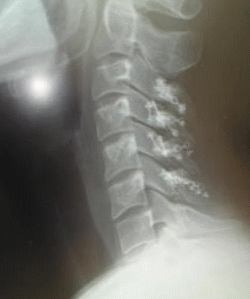

脊髄髄内腫瘍のCT画像(手術後)

撮影日:2010年1月15日

問題点:2か所

①チタンプレートが真ん中で折れている

②スクリュー(ねじ)とチタンプレートが外れている

おそれく手術後の割と早い段階で、折れたり外れたりした様子ですがそうなった原因は不明

折れたり外れたりしていても、きちんと人工骨の上に自分の骨が再生しているので問題は無いし、手術も必要ではないそうです